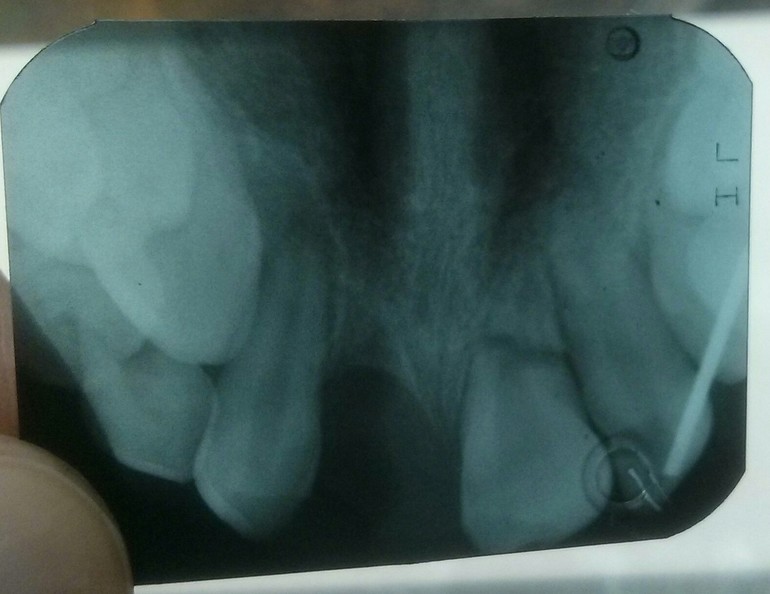

Вот такая печальная картина

18.09.2019

Да, картина плоха тем, что сделали панорамный ради 4 зубов, а их как-то плохо видно в итоге.

Да, все через жопу в нашем го..: аппарат какой-то сломался, делали на другом, в итоге плохо видно. Спасибо. Будем надеяться на лучшее